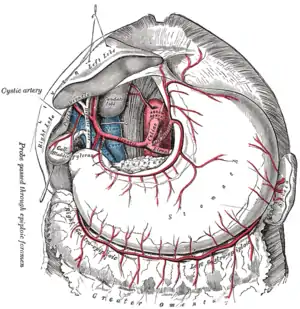

Splanchnic Circulation

This includes the blood supply and drainage - via the portal system - of the gut as well as the pancreas, liver and spleen. The liver is drained by the hepatic vein.

Gastrointestinal blood supply

Blood supply comes from three arteries branching off the aorta: the coeliac artery, the superior mesenteric artery, and the inferior mesenteric artery.

Coeliac Artery

Supplies blood to the stomach, liver, pancreas and spleen as well as the duodenum.

Superior Mesenteric Artery

Supplies blood to the small intestine as well as the superior part of the colon. Notice the system of arching anastemoses that is a feature of the splanchnic arteries.

Inferior Mesenteric Artery

Supplies blood to the colon. Again notice the system of arching anastemoses.

Hepatic Portal System

All the blood from the GI system below the esophagus drains into the hepatic portal vein. The portal system also drains the spleen and pancreas. Blood is conveyed to the liver for processing where it passes through millions of liver sinusoids. This allows the reticuloendothelial cells that line the sinusoids to remove bacteria and other particulate matter. Blood finally leaves the liver via the hepatic vein where it drains into the inferior vena cava.

The total blood flow to the liver is about 1.5 liters per minute, of which two-thirds is carried by the portal vein. The blood in the portal vein is more oxygen-saturated than blood in the systemic venous system; it is about 80-90% saturated and provides about 70% of the oxygen requirements of the liver.